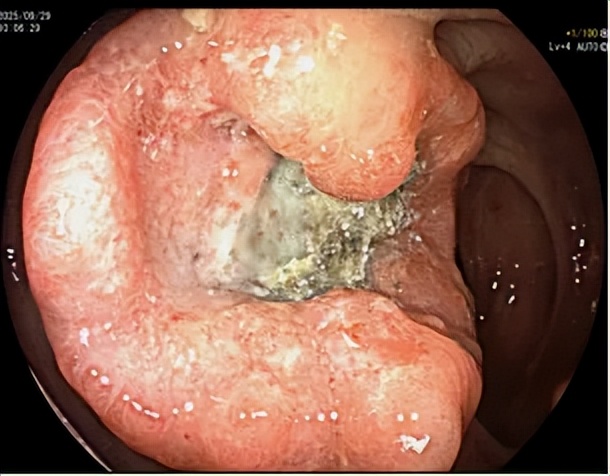

當(dāng)內(nèi)鏡進(jìn)入腸道,景象讓唐瀟醫(yī)生心里一沉:十年前的乙狀結(jié)腸和直腸息肉,已從可輕松摘除的“小疙瘩”,演變成形態(tài)不規(guī)則、質(zhì)地脆爛、極易出血的癌性病灶。

直腸的息肉同樣未能幸免,已進(jìn)展為進(jìn)展期直腸癌。

唐瀟醫(yī)生表示:“檢查結(jié)果顯示,陳先生體內(nèi)有兩處原發(fā)腸癌灶。這意味著他要面對(duì)創(chuàng)傷更大、恢復(fù)更慢的外科手術(shù),甚至可能需要后續(xù)放化療?!?/p>